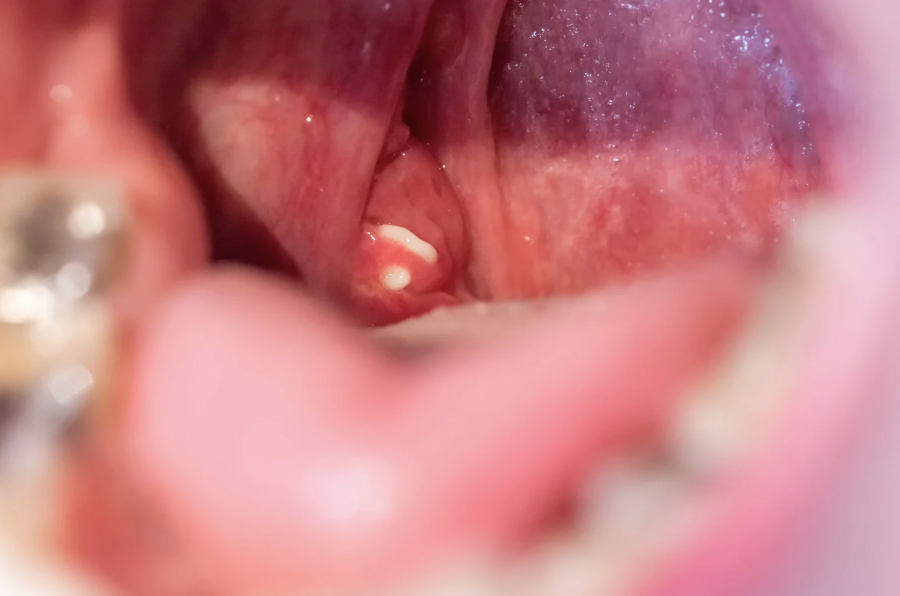

Common symptoms include swollen tonsils, painful or difficult swallowing, red throat, high-grade fever, and white or yellow patches on the tonsils. Enlarged neck glands, sore throat, muffled or altered voice, headache, low appetite, and ear pain are also frequent. Some individuals experience breathing difficulty through the mouth, persistent bad breath, fatigue, nausea, or voice changes. In some cases, tonsilloliths or tonsillitis develop when debris becomes trapped. Occasionally, tonsils may enlarge enough to touch each other, a condition described as “kissing tonsils,” which may further obstruct airflow.

Repeated or chronic inflammation of the tonsils may lead to certain complications. These include respiratory difficulty, particularly in children with markedly enlarged tonsils. Obstructive sleep apnea may result from interrupted airflow during sleep. Tonsillar cellulitis can develop if the infection spreads into deeper tissues. In some cases, a peritonsillar abscess may form, causing severe pain and requiring timely medical attention. These potential complications highlight the importance of monitoring persistent tonsillitis symptoms.

Diagnosis usually begins with a clinical examination of the throat, where enlarged, red, or swollen tonsils may be observed, along with inflamed lymph nodes. The doctor may also assess associated symptoms such as fever, voice changes, difficulty swallowing, or breathing discomfort.

Collection of pus near the tonsil causing intense pain, swelling, and difficulty opening the mouth.